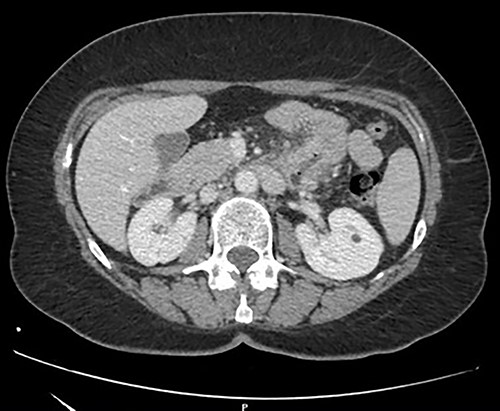

A 57-year-old woman was admitted in our General Surgery department lamenting fatigue, diffuse abdominal pain and dyspepsia. The patient had no previous history of abdominal surgery or pre-existing conditions. On physical examination, there were no signs of abdominal masses or tenderness. Contrast-enhanced computed tomography showed a soft tissue mass of the duodenojejunal junction with initial signs of narrowing of the lumen (Fig. 1). We decided to perform a duodenojejunal resectionwith open approach. The tumor showed signs of extra-serosal extension and infiltration of the transverse mesocolon, the mesentery and the inferior mesenteric vessels. A complete abdominal exploration ruled out the localization of peritoneal carcinosis. Kocher maneuver was performed, and the tumor was resected en bloc with a portion of transverse mesocolon and mesenteric peritoneum. The intestinal continuity was restored with a linear stapled duodenojejunal side-to-side anastomosis (Fig. 2). The post-operative course was uneventful, and the patient was discharged on IX POD. Histological examination showed a poorly differentiated signet-ring cell adenocarcinoma of the small bowel, pT4 pN0 (0/19) pM1 (peritoneum) R0, L1, V1, Pn1, infiltrative tumor margin, tumor budding was present. During oncological follow-up, the patient was administered with 11 cycles of FOLFOX. Thirteen months later, the patient presented to the emergency department with recurrent episodes of vomiting and upper abdominal pain. A contrast-enhanced CT scan showed a relapse with intestinal obstruction. A re-laparotomy was performed; a fibrous and firm hernia sac was resected and sent to extemporaneous histopathological examination, showing localization of carcinomatosis. Diffuse miliary peritoneal carcinomatosis was present; therefore, we decided to perform a palliative duodenojejunal bypass. Post-operative course was uneventful, after an oral contrast CT the patient was discharged on IX POD. Unfortunately, the patient passed away 3 months after the palliative procedure.